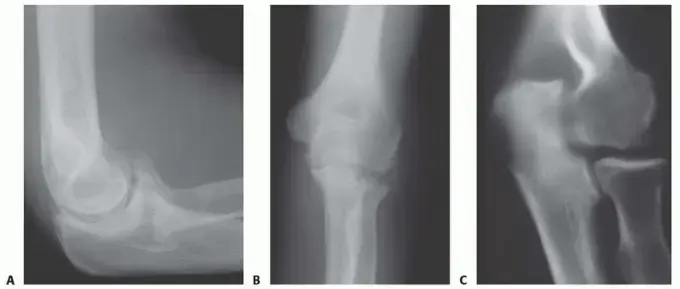

* الأشعة السينية (X-rays): تُظهر الأشعة السينية عادةً تكوّن نتوءات عظمية على عظمتي الزند والعضد، خاصةً على الناتئ الإكليلي (Coronoid) ولقمة الزند (Olecranon). في المراحل المبكرة، قد يكون الفراغ المفصلي بين العظام محفوظًا نسبيًا، لكن في المراحل المتقدمة، يظهر ضيق ملحوظ في الفراغ المفصلي.

تُعد عملية تنظيف المرفق بتقنية أوتربريدج-كاشيواغي إجراءً فعالًا لعلاج خشونة مفصل المرفق الأولية، خاصة في المراحل التي تتميز بالألم في أقصى مدى الحركة، مع وجود نتوءات عظمية واضحة في الأشعة السينية، بينما لا يزال الفراغ المفصلي محفوظًا نسبيًا.

وُصفت هذه العملية لأول مرة عام 1978 وحظيت بشعبية واسعة بعد بضع سنوات. تُركز على إزالة العوائق العظمية التي تُعيق حركة مفصل المرفق الزندي العضدي.